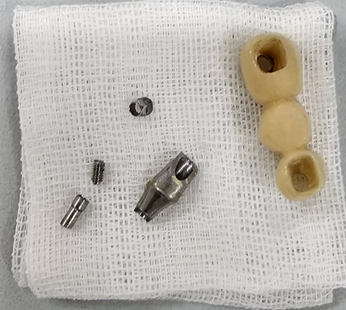

“zig는 어떻게 연결 하나요?”

“어버트먼트 파절됐는데 어떻게 하나요?”

이런 디테일한 것도 모두 알려드립니다

55-1픽스쳐종류와 타입17min

임플란트 픽스쳐종류에 대해 알아보고 여러가지 픽스쳐 종류를 구분하고 이해할수있게된다.

65-2어버트먼트 종류마스터17min

피스쳐와 그상부 구조물인 어버트 먼트 종류에 대해 알아보고 많은 어버트먼트중에 종류를 구분지을수있게 된다

97.임플란트 보철 셋팅준비19min

임플란트보철셋팅준비물 부터 임플란트후 관리까지 방법에대해 알수있다.